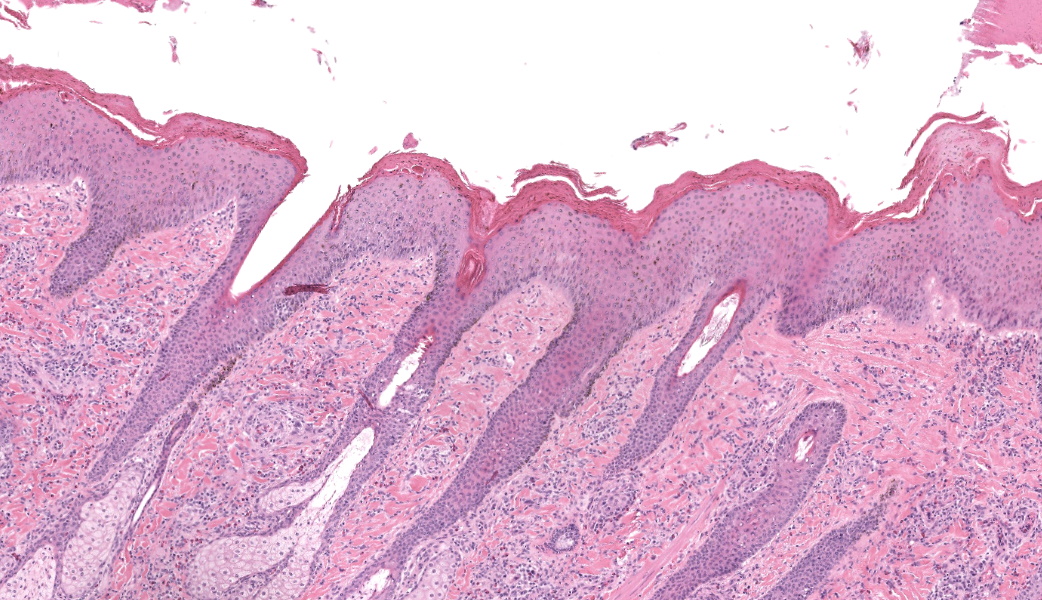

Haired skin, coronary band. Expanding and infiltrating the entire dermis are multifocal to coalescing perivascular, periadnexal and interstitial aggregates of moderate numbers of lymphocytes, eosinophils and histiocytes, fewer plasma cells and occasional neutrophils. Multifocally within dermis are few small areas of intensely eosinophilic, fragmented collagen fibers admixed with eosinophilic cellular- and basophilic nuclear debris, surrounded by epitheloid macrophages and multinucleated giant cells (eosinophilic granulomas). Intramurally and intraluminally within multiple hair follicles are moderate numbers of eosinophils, lymphocytes and histiocytes and few multinucleated giant cells (mural and luminal folliculitis), and adjacent follicular epithelium display moderate spongiosis. In the dermal-epidermal interface, there is a multifocal mild edema. The epidermis shows mild lymphocytic infiltration, mild spongiosis and occasional apoptotic keratinocyte, diffuse mild acanthosis and mild rete ridge formation (epidermal hyperplasia), moderate parakeratotic and orthokeratotic hyperkeratosis and multifocal erosions and ulcerations, the latter being covered by large serocellular crusts spanning over several adnexal units. Serocellular crusts show abundant viable and degenerated neutrophils, occasional eosinophil, cellular debris, fibrin, free keratin and hair fragments and occasional small basophilic bacterial colonies. There are also small epidermal intracorneal pustules multifocally. Several arteriolar walls in deep dermis show infiltration of few eosinophils and lymphocytes (vasculitis). The deep dermis displays mild diffuse edema.Contributor's Morphologic Diagnoses:

Haired skin, coronary band: Dermatitis and folliculitis, lymphoplasmacytic, histiocytic and eosinophilic, multifocal to coalescing, moderate, with eosinophilic granulomas, epidermal intracorneal pustules, serocellular crusts and orthokeratotic and parakeratotic hyperkeratosisEquine multisystemic eosinophilic epitheliotropic disease (MEED)

The contributor’s comment in this case provides an exceptional overview of multisystemic epitheliotropic eosinophilic disease (MEED) in horses and its major differentials, all of which were discussed during conference. MEED is currently considered to be an abnormal manifestation of inflammatory bowel disease (IBD) in horses. The cutaneous manifestation of MEED classifies as a perivascular dermatitis pattern, and the depth of inflammation and affected vasculature can assist with the diagnosis of MEED compared to others that would be confined more to the superficial dermis (i.e. insect bite hypersensitivity). Conference participants ultimately all agreed with the contributor’s diagnosis of MEED in this case.If lesions are restricted to the GI tract, other causes of inflammatory bowel disease, intestinal parasitism, and idiopathic focal eosinophilic enteritis (IFEE) should rise higher on the differentials list. There was an excellent case of IFEE seen earlier this year in Conference 1, Case 3, the contributor of which provided a fantastic comparison between IFEE and MEED in their comment. Additionally, a thorough overview of eosinophils was covered in the JPC comment for Conference 2, Case 3 this year as well, and those two comments are great supplementals to this case.